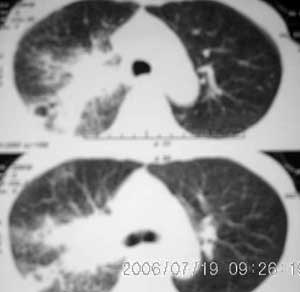

以下是引用jiangjing在2006-7-20 19:22:00的发言:[br]右侧肺门见有软组织肿块,边缘不规则,不光整,其周围肺内见炎性片状影,胸片示水平裂呈弧形上移,右上叶支气管狭窄,考虑右肺中央型肺癌伴阻塞性肺炎部分肺不张。

以下是引用1983在2006-7-20 21:53:00的发言:[br]右侧中央型肺癌伴阻塞性肺炎.

以下是引用卜一在2006-7-20 14:13:00的发言:[br]图象质量差了些,首先考虑:中心性肺癌伴阻塞性肺炎.因发生在右肺上叶尖后段,而且外带见二个空洞影,次考虑:不排除肺结核